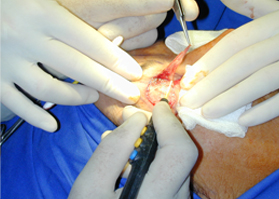

適合于皮下組織的切割和剝離。

特別是在運血較為豐富的部位。

適合于要求良好止血的切割。